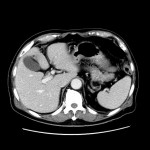

CT検査

当院では各診療科からの検査依頼があり、診断用CTが2台、放射線治療計画用CTが1台稼動しています。

CTの原理を簡単に説明します。

CTの寝台に寝ていただき、その寝台が動きながら検査を行います。寝台がガントリー(X線発生器と検出器等から構成)と呼ばれるドーナツ状の機械を通過する際に、X線を照射し、検出しています。物質のX線の吸収差を利用して、360度方向からのデータを再構成することで輪切りの画像が完成します。空気や水などX線を吸収しにくいものは黒く、骨などX線を吸収しやすいものは白く表示されます。

また、造影剤を静脈から注射することで区別が難しかった目的の臓器や病変も見やすくなります。しかし副作用のリスクがあるためヨード過敏症の方や過去に副作用が出現した方、腎臓の機能が悪い方は主治医にお申し出ください。

当院のCT装置の最薄スライス厚は0.625mmで、これにより一つの断面だけでなくいろいろな角度からの断面を構築することや、血管や骨の3次元表示を可能にしています。また、2021年2月に導入された装置では、2種類のエネルギーを使用して撮影することで、コントラストの増強、アーチファクトの低減、さらに特定の物質を強調したり抑制した画像が作成でき、診断能の向上が見込めます。

CTについてわからない点や不安なことがありましたら担当の技師または看護師にご相談ください。